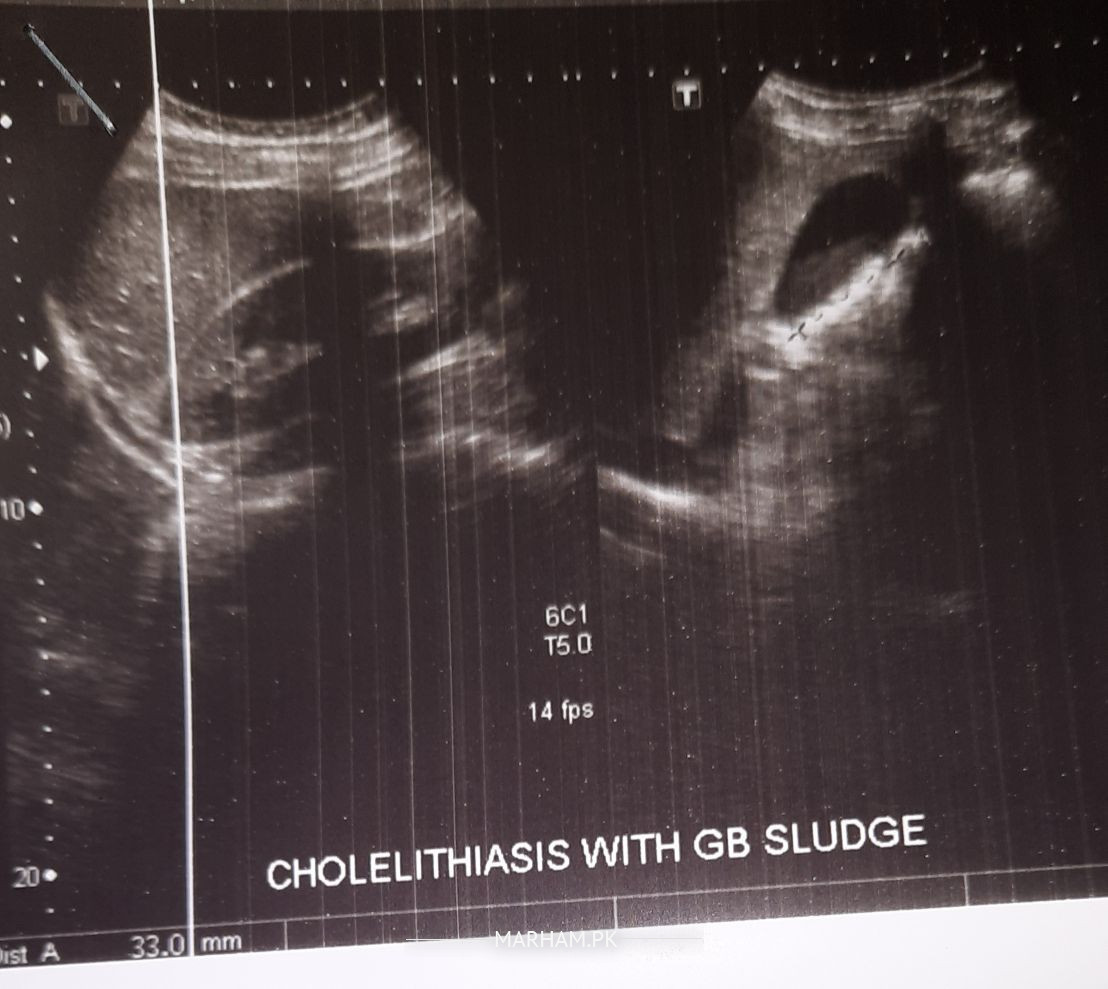

I have multiple gallstones and one of them is 3.3 l, doctor recommended me for surgery and I'm willing to proceed with it but not to take off the gallbladder just wash it. please refer someone who's having expressive such kind of cases